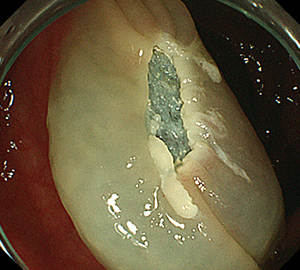

ESDは2cmを超える大きな病変でも、病変を分割することなく一括で切除するために開発された治療法です。専用のナイフを用いて病変の端から少しずつ確実に剥離して一括切除します。一括切除することで病変の正確な評価が可能となり、癌が取りきれたか、どこまで深く浸潤しているかなどを判定し再発リスクや追加治療の必要性が適切に判断出来ます。

1回の切除で完全な切除ができますので、治療後の再発はほとんどありません。

ESDの入院期間は病変の大きさや手術時の状況にもよりますが概ね7-9日で行っています。